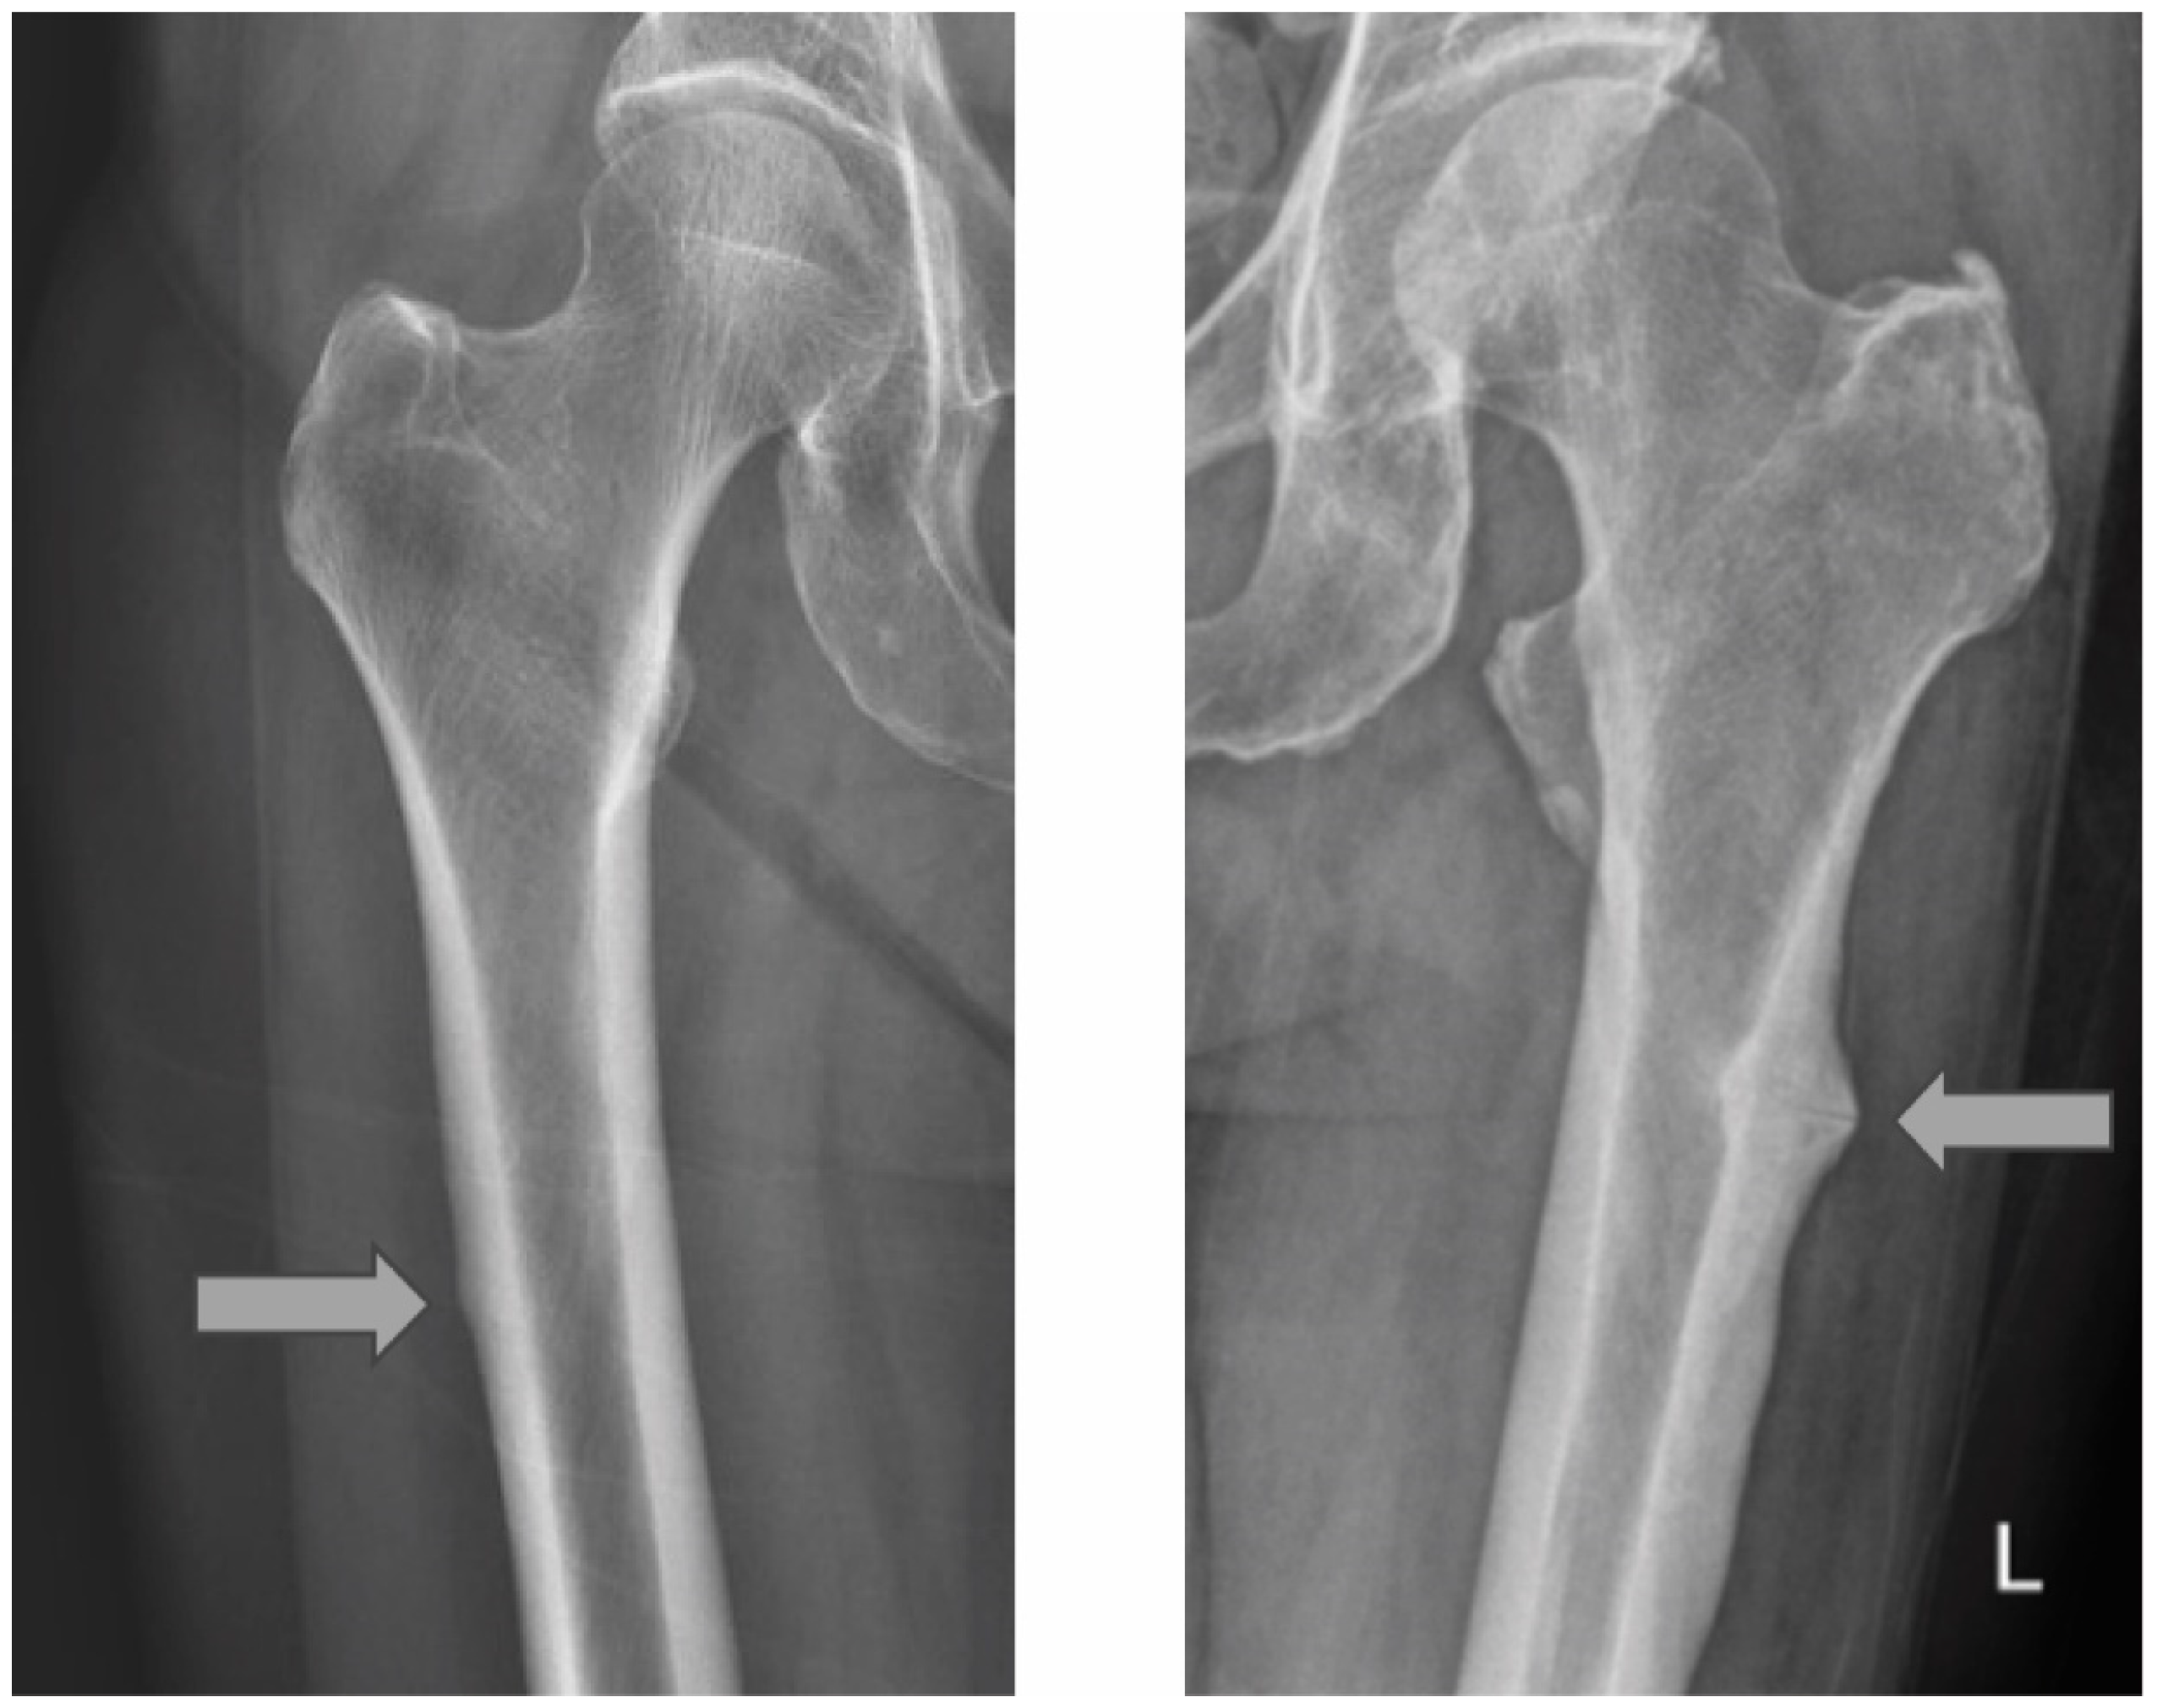

| Union | Non-Union | Total | |

|---|---|---|---|

| Subtrochanteric | 44 (93.6%) | 3 (6.4%) | 47 |

| Diaphyseal | 21 (95.5%) | 1 (4.5%) | 22 |

| Total | 65 (94.2%) | 4 (5.8%) | 69 |